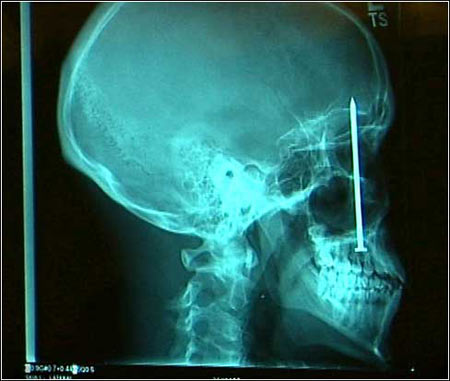

他被钉住了:1月6日,X光片显示,一只4英寸的钉子钉在了23岁的美国人Patrick Lawler的头颅里。这只钉子可能在一次事故中被射钉枪钉进了他的头里,但后来得以康复。直到最近,Patrick到诊所看牙病才发现了它